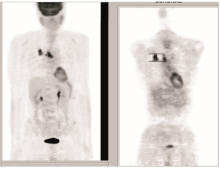

2009-09-03 PET/CT示右肺上叶肿块及纵隔内气管前、隆突下、肺门淋巴结代谢增高,考虑为周围型肺癌并肺门纵隔淋巴结转移可能性大,见 图3;支气管镜示气管及支气管呈炎症性改变。